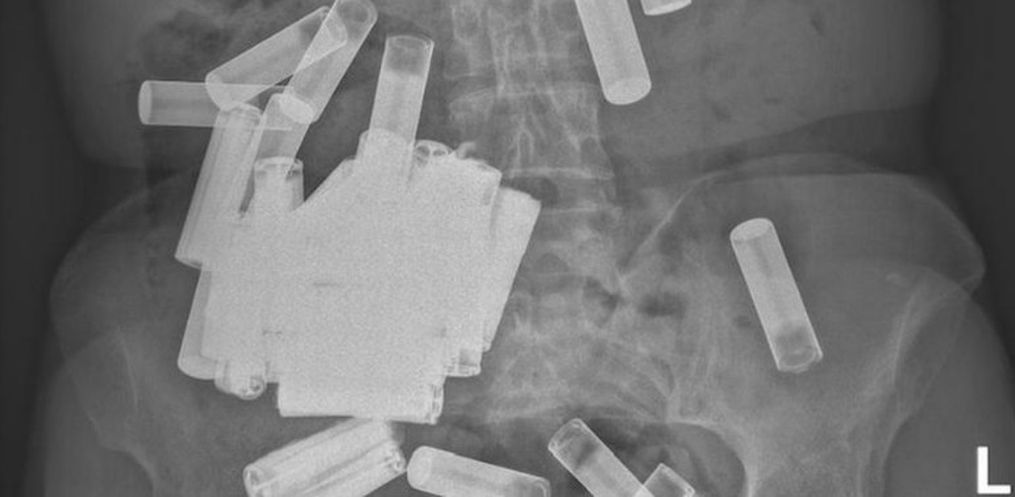

Durante uma consulta no hospital Saint Vincent’s University, em Dublin, na Irlanda, médicos descobriram que uma mulher havia ingerido 55 pilhas. Localizados no estômago e no intestino da mulher de 66 anos, os objetos foram identificados por meio de um raio-X.

Os profissionais do hospital analisaram o estado de saúde da mulher, que estava bem e sem nenhuma obstrução no sistema gastrointestinal. Eles concluíram que ela iria liberar de forma natural — pelas fezes — todas as pilhas.

Segundo um estudo do caso publicado no Irish Medical Journal no dia 15, na primeira semana, ela conseguiu liberar cinco pilhas AA. Os outros objetos ingeridos não foram liberados, e ela passou a sentir dores no estômago.

Aos 66 anos, ela passou novamente por exames, e os médicos decidiram retirar as 46 pilhas por meio de uma cirurgia, já que o estômago da paciente estava distendido. O órgão ficou pendurado acima do osso púbico por causa do peso das pilhas.

A cirurgia foi efetiva, mas ainda sobraram quatro pilhas. A mulher precisou passar por um processo de "ordenhação" para a retirada do restante, que saiu pelo intestino. Uma última radiografia revelou que a paciente estava sem baterias no corpo.

"Até onde sabemos, este caso representa o maior número relatado de baterias ingeridas em um único ponto no tempo", afirmou o jornal médico.

As 55 pilhas engolidas variavam entre os tipos AA e AAA. Os médicos destacaram o perigo da ingestão de objetos: "O potencial das baterias cilíndricas para resultar em emergências cirúrgicas agudas não deve ser subestimado". Esse tipo de ingestão pode causar lesão da mucosa, perfuração e também obstrução, de acordo com informações dos médicos.